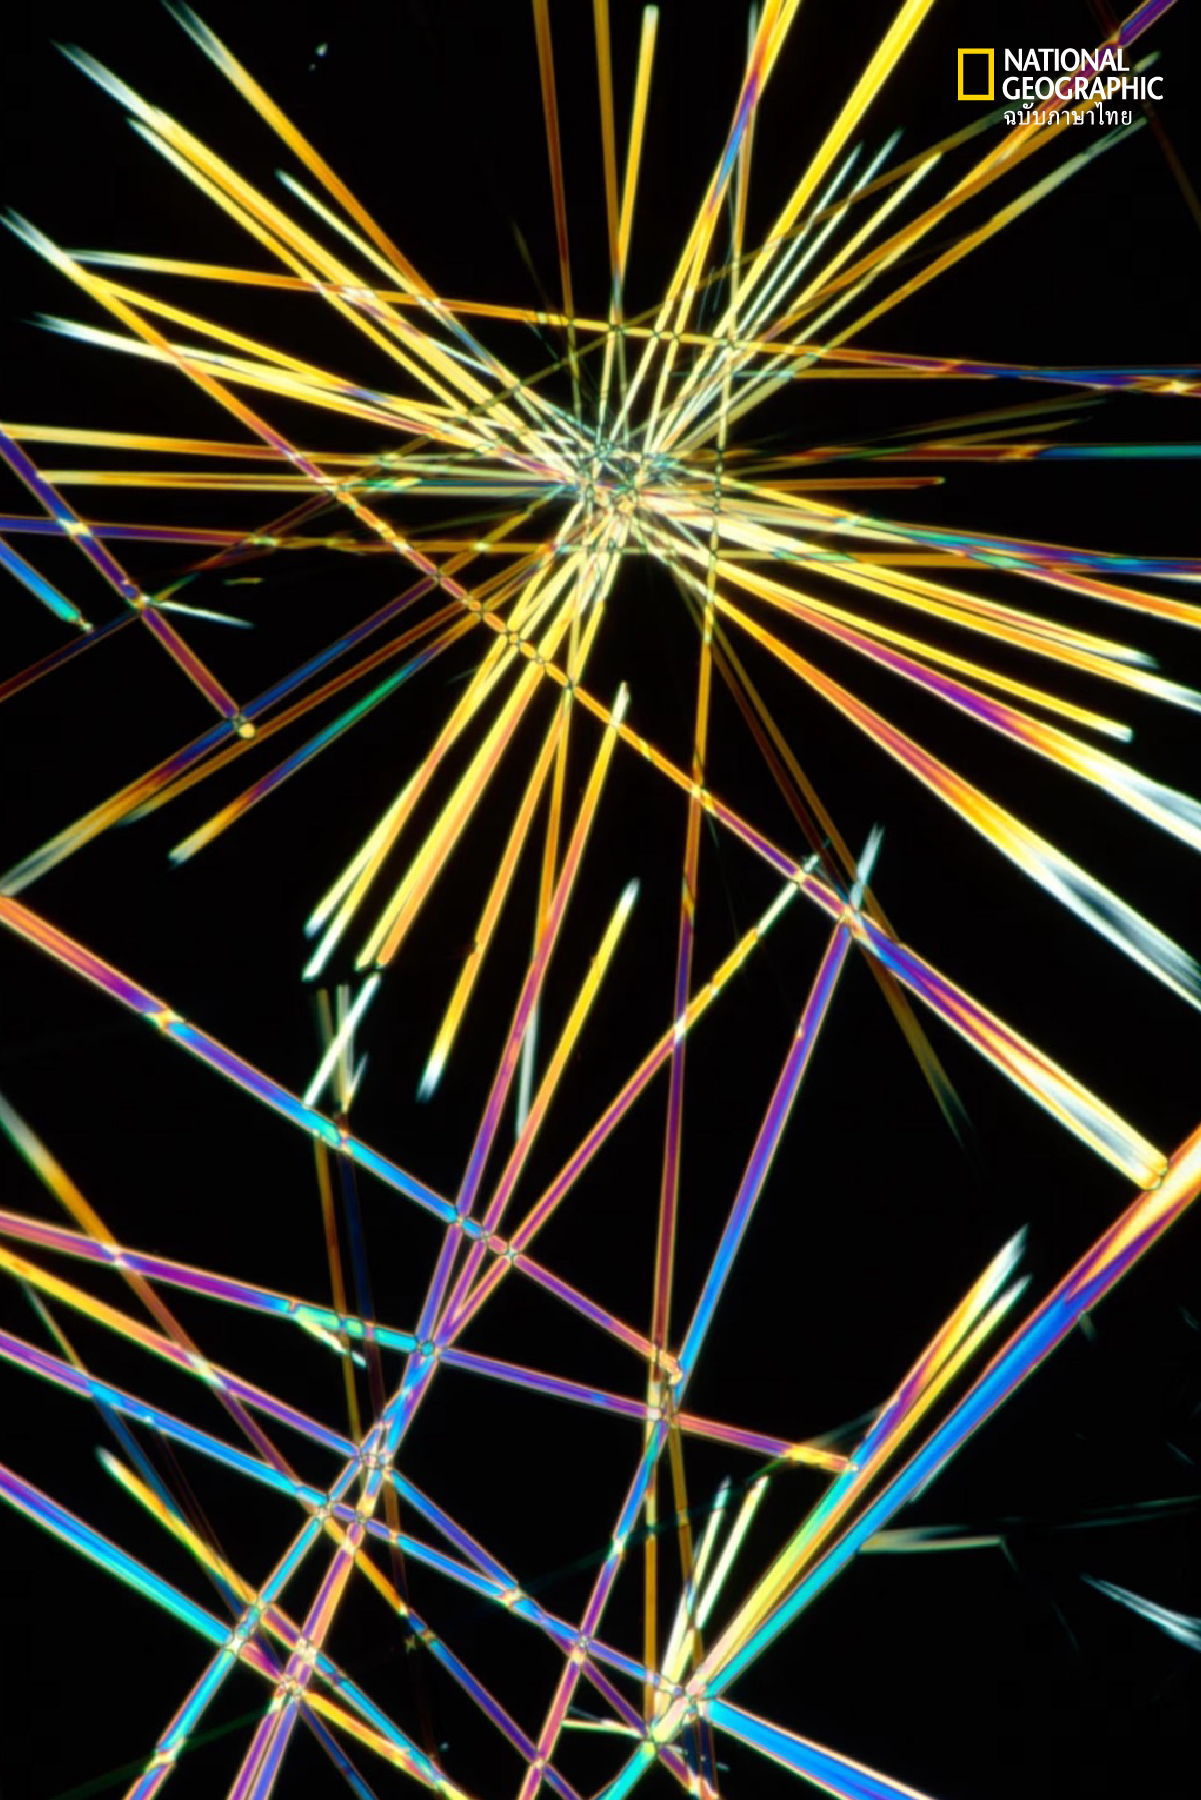

“ตัวคาเฟอีนนั้นมีฤทธิ์ที่ช่วยป้องกันการเกิดไมเกรนได้ดี” อิหมัด เอสเตมาลิก อายุรแพทย์เฉพาะทางด้านประสาทวิทยาของคลินิก Cleveland ในรัฐโอไฮโอ สหรัฐอเมริกา กล่าว พร้อมเสริมว่า มียารักษาไมเกรนหลายชนิดที่ผสมคาเฟอีนลงไปเพื่อเสริมการออกฤทธิ์ให้ดีขึ้น